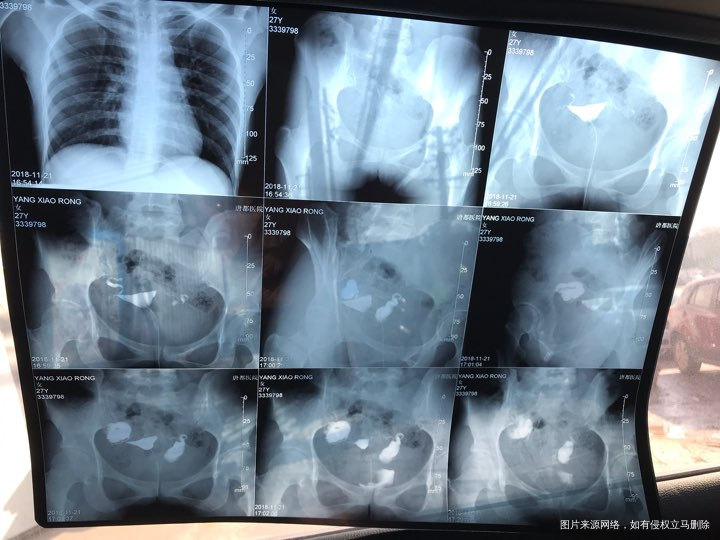

备孕时常1年,前期的检查都做了正常,帮忙看下我的输卵管造影片子吧??

您好,看着像是伞端堵塞了。

您好,考虑输卵管堵塞。建议遵医嘱。

您好,输卵管堵塞,建议切除输卵管做试管,保守保守治疗没有多大意义,觉着我的回复对您有帮助记着帮忙点击采纳,谢谢!